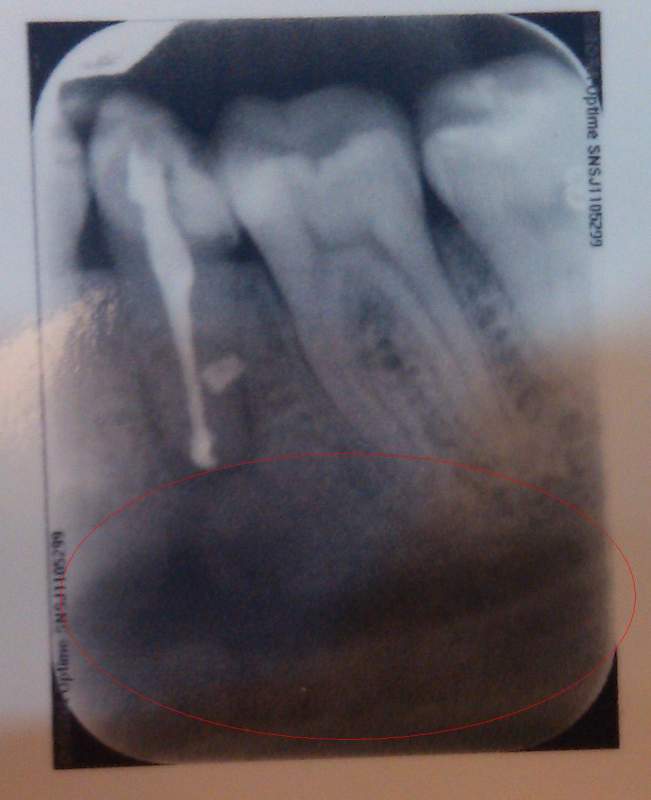

Çë½Ì¸÷λ´óÉñ£¬¹ØÓÚ¸ù¼âÄÒÖ׸ù¹ÜÖÎÁƺóµÄÑÀƬ ÒÑÓÐ2È˲ÎÓë